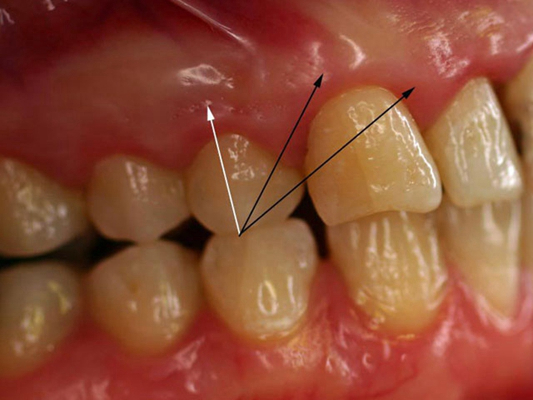

牙齦炎

牙齦炎圖片

牙齦炎和牙周炎